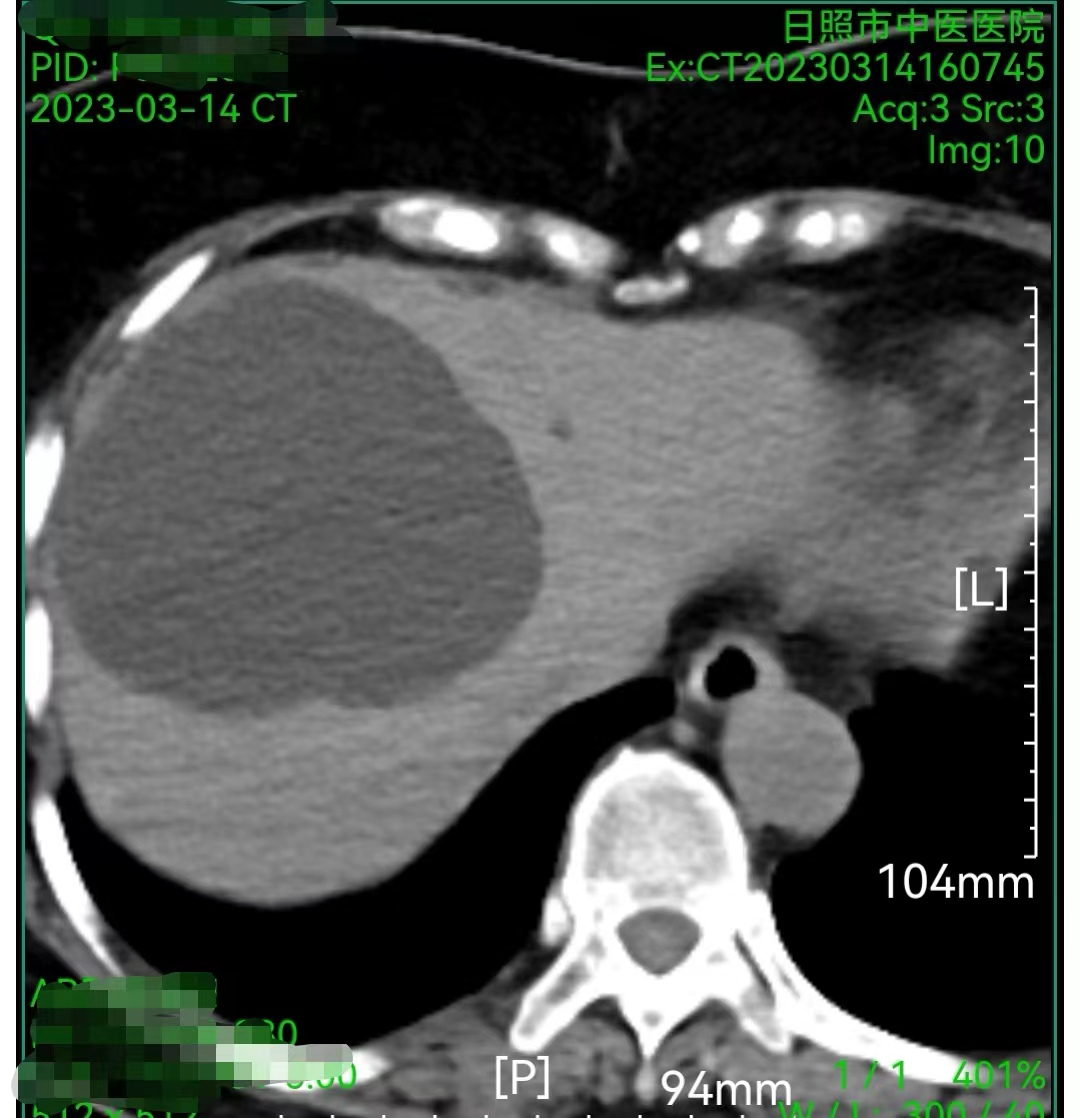

近日,日照市中医医院通过多学科协作,为一名65岁右肝巨大囊肿的患者行CT引导下穿刺置管引流术及CT引导下肝囊肿穿刺硬化术,术后患者恢复良好出院。

患者因腹胀、腹部不适就诊脾胃病二科/肝病科,系统检查提示右肝巨大囊肿,几乎占据整个右肝的二分之一,继续发展将严重压迫胃肠道及周边脏器,出现腹痛、腹胀,肝功能不全等并发症。

图1.穿此前腹部CT提示右肝巨大囊肿图1大囊肿